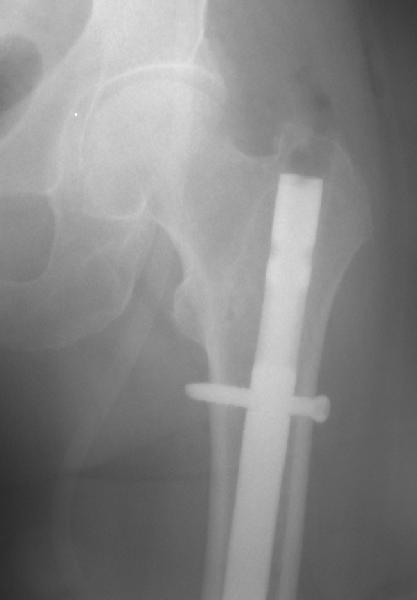

То, что планируется - наиболее распространенный подход. Еще менее инвазивный вариант - закрытый антеградный интрамедуллярный остесинтез. Мы используем гвозди, которые выпускаются предприятием ЦИТО, т.е. недорогие. Там в дистальное отверстие можно ввести 3 винта (2 снаружи и один навстречу), еще и угловая стабильность получается.

Приходится индивидуально делать под конкретную ножку, с предпритием ЦИТО это получается за несколько дней и недорого.